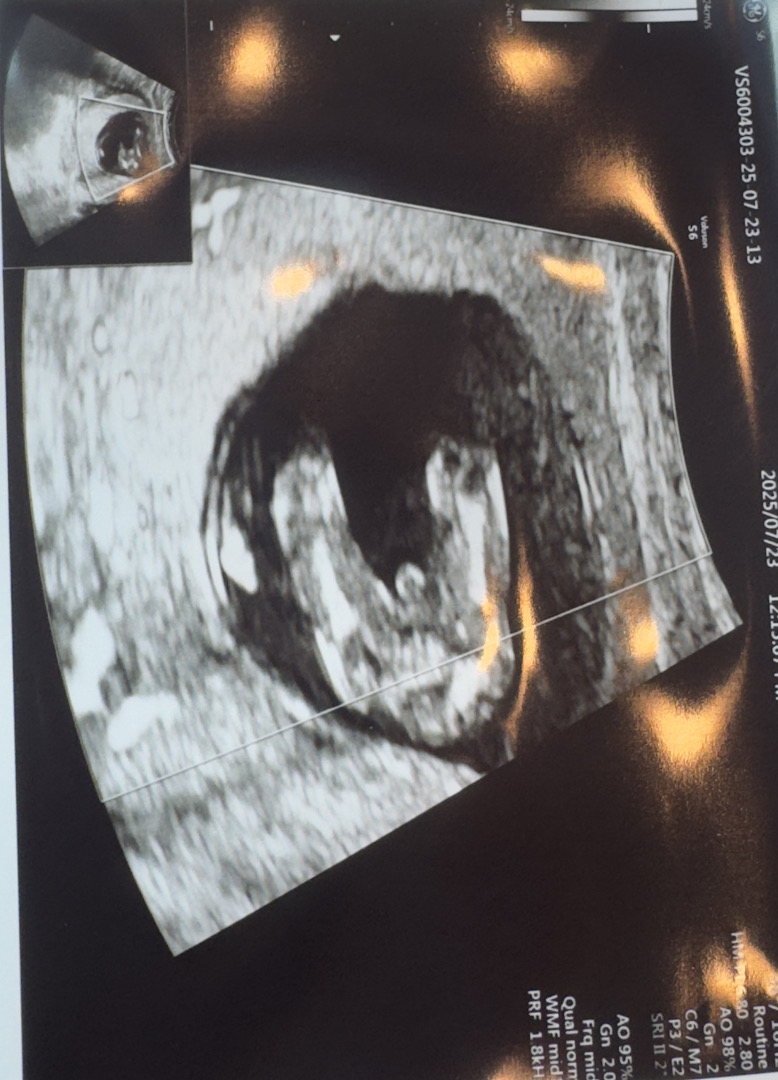

빼박 아들인거죠 ?

빼박 아들인거겠죠 ?!!

굵은거보니까 탯줄일수도 잇어요 ! 저 초음파 이렇게 찍혓는데 딸이에욥